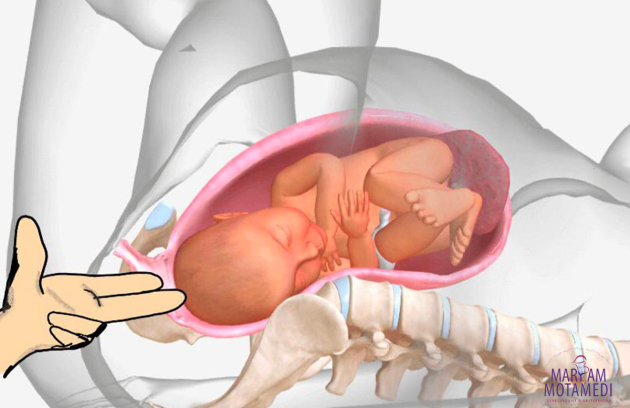

بارداری دوقلو، یکی از پدیده های شگفت انگیز و جذاب در دنیای پزشکی و زایمان است. بسیاری از خانوادهها به…

چگونه چندقلو باردار شویم؟